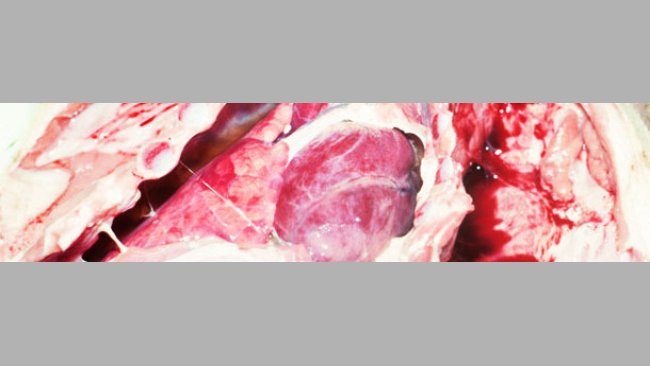

Este caso clínico estuda o comportamento e o controlo, a longo prazo, de uma infecção por App num ciclo fechado, abordando aspectos importantes como o desenho da exploração, a dinâmica da infecção e a evolução da imunidade.